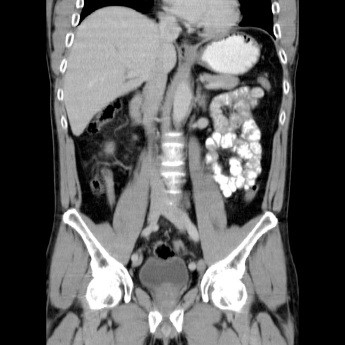

КТ брюшной полости – метод диагностики, который описывает состояние внутренних органов брюшной полости (вместе с сосудами и абдоминальными лимфатическими узлами) и забрюшинного пространства послойно с величиной шага от 0,5 до 10 мм.

Компьютерная томография дает информативное высокоточное трехмерное изображение, выявляя такие небольшие изменения в органах, которые невидимы при других исследованиях. Высокая скорость сканирования дает возможность получить результаты уже через 2 часа, а низкая лучевая нагрузка на тело человека расширяет показания к применению. При КТ возможно дифференцировать ткани за счет разницы их плотности с точностью 0,5%.

КТ описывает структуру паренхиматозных органов, ее болезненные изменения, проходимость трубчатых органов.

КТ брюшной полости способна показать объемные процессы патологических изменений (размеры очага воспаления, его границы и степень распространения) и сбой в функциональности органов, а именно: